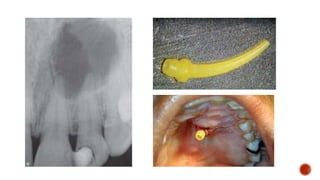

 PDL injections are usually given

using either a standard dental

anesthetic syringe or a high-

pressure syringe.

Special pressure needles have been developed for IL injection with Preset

volume (0.14-0.22 mL) with minimal effort.

27 or 30 G needle inserted with positive pressure as deep as possible along

the root with the bevel towards the crest.

In posteriors, needle is bent to an angle and trigger is squeezed to deliver

0.2 mL

Immediate onset and lasts 27 minutes

92% effective